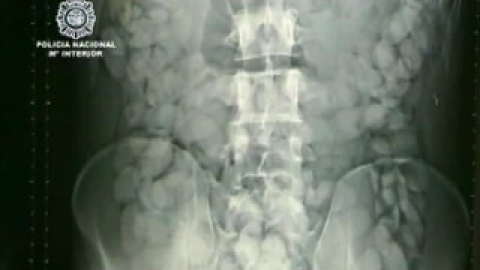

Con 270 'bellotas' de hachís en el cuerpo

España ÚLTIMA HORAEn directoLa guerra iniciada por Israel y EEUU se extiende por Oriente Medio mientras Irán anuncia nuevos ataquesÚLTIMA HORAEn directoLa guerra iniciada por Israel y EEUU se extiende por Oriente Medio mientras Irán anuncia nuevos ataques Con 270 'bellotas' de hachís en el cuerpo Ver vídeoVer en DailymotionTamaño de letraColor de fondoCompartePolicía Nacional31/03/2010 16:57Con 270 'bellotas' de hachís en el cuerpoComparte